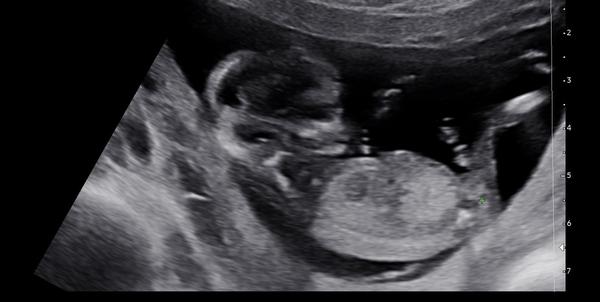

Dokáže lékař odhadnout pohlaví v 13. týdnu?

Ahoj všichni! Doktor mi dnes ve 13. týdnu řekl, že odhaduje kluka. Hodně jsem četla, že v brzkých týdnech je to celkem nerozeznatelné. Dokáže někdo třeba porovnat se svým ultrazvukem? Popř. Trefil se doktor vám?